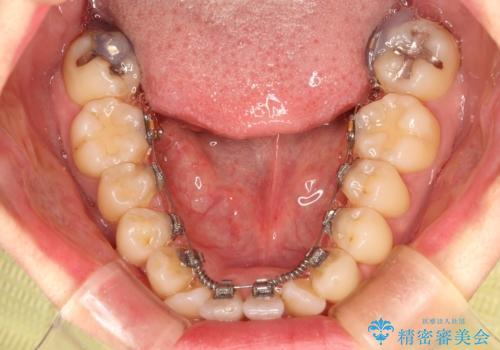

フルリンガル矯正 非抜歯でガタつきを整える

- フルリンガル

- フルリンガルワイヤーによる非抜歯治療を計画しました。

フルリンガルは違和感も強く操作も煩雑になるため、あまりおすすめはしていませんが、お仕事の都合などでどうしても装置を付けられない&マウスピースを管理することができない、場合はやむなく選択することもあります。